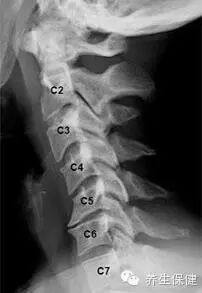

怎樣才能知道自己的頸椎是否健康?日常生活中身體發出的小信號會提示不同類型的頸椎問題。

信號一:長時低頭伏案工作,感覺到頭暈難受,考慮為椎動脈型頸椎病;

信號二:不明原因的肩頸痠痛,手臂發麻,考慮為神經根型頸椎病;

信號三:正常直行走路卻常出現「跑偏」問題,考慮為脊髓型頸椎病;

信號四:經常有不明原因的頭暈、眼花、耳鳴、手麻、心動過速、心前區疼痛等一系列症狀,考慮為交感神經型頸椎病。

如果同時出現上述幾類症狀,則考慮為混合型頸椎病。